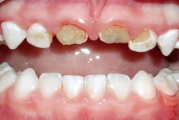

Vali sind huvitav pilt ja me näitame sellega seotud haigust ja sümptomeid